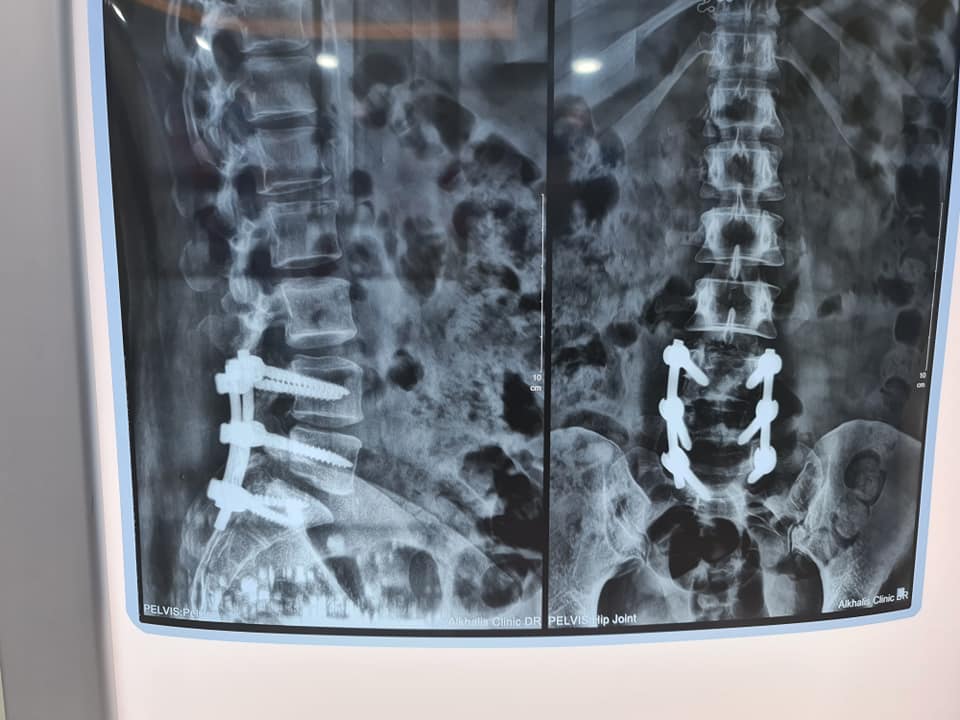

- من خلال إجراء الجراحة لعلاج الحالات المعاندة والغير المستجيبة.